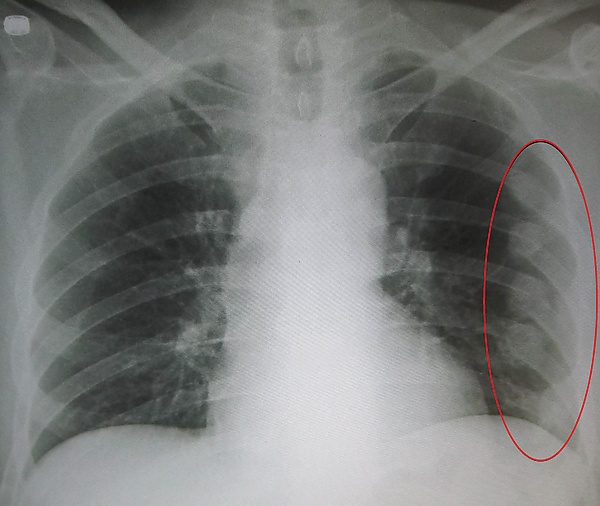

Диагностика

Проводят рентгенографию грудной клетки. Однако при данном методе не всегда удаётся выявить перелом. Поэтому диагноз перелома рёбер обычно устанавливают на основании клинических данных (анамнез, жалобы, объективные данные). Для исключения осложнений проводят клинический анализ крови и мочи.